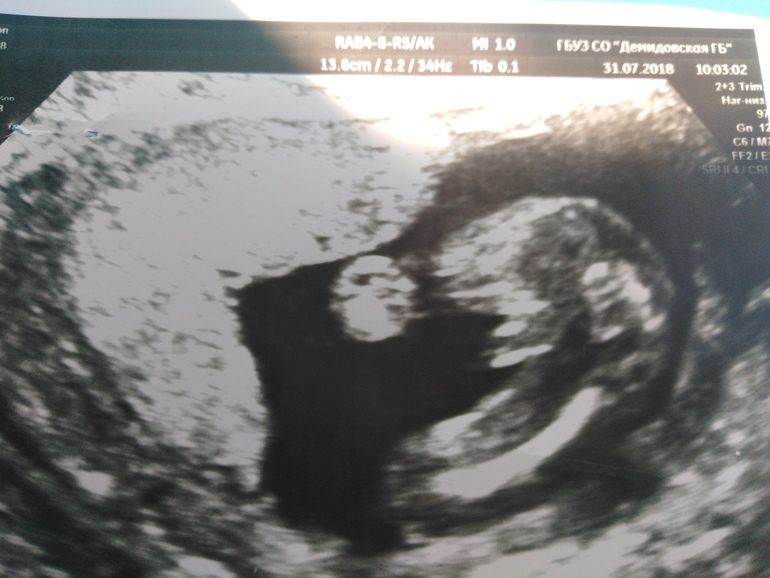

За неделю до скрининга ходила на цервикометрию у себя в городе.Дали фото для папы ,чтобы точно видел кого ждёт.